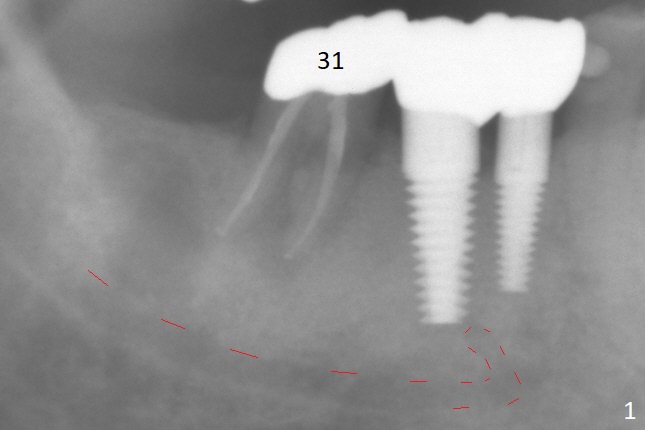

A 87-year-old man was asymptomatic with the tooth #31 eight months earlier (Fig.1), as compared to now (Fig.2). After extraction, osteotomy will be initiated in the septum (where there is more bone height) using IS 6 mm stopper (Fig.3 red line), followed by PA. If PA does not show the Inferior Alveolar Canal (Fig.1 red dashed line), take panoramic X-ray. A 5.5x13 mm implant will be placed (7 mm may not be covered by the native bone). The mesial root vertical root fracture is more obvious 7 months later (Fig.4,5).